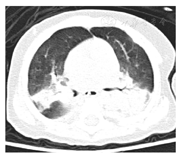

10例SCID患儿中,男8例,女2例,男∶女为4∶1;平均发病年龄4.2个月,平均诊断年龄6个月;10例患儿均诊断肺炎,其中9例患儿肺CT提示重症肺炎(图1),且8例胸腺影缺如,3例(例1、4、9)并发肺部真菌感染;其中1例(例10)注射卡介苗后发热,注射部位红肿破溃,同侧颈部及腋下淋巴结肿大,考虑其为播散性卡介苗病可能(图2);10例患儿中有4例(例1、2、5、10)存在家族史,例1患儿母亲舅父生后不久死亡;例2患儿哥哥于出生3个月时因持续低热、肝脾大、周身皮疹,于当地医院救治无效死亡;例5同胞兄长因重症肺炎于1岁死亡;例10患儿母亲前2个孩子分别于2岁及6个月夭折。本组10例患儿中,7例死亡,1例失访,2例患儿存活,病情好转,已经接受配型,目前等待移植中;死亡的7例患儿中,除例2为造血干细胞移植术后发生免疫排斥反应死亡外,其余6例均为感染后死亡;7例患儿死亡年龄均不超过1岁,见表1。

双肺多叶段炎症,局部实变;未见胸腺影。